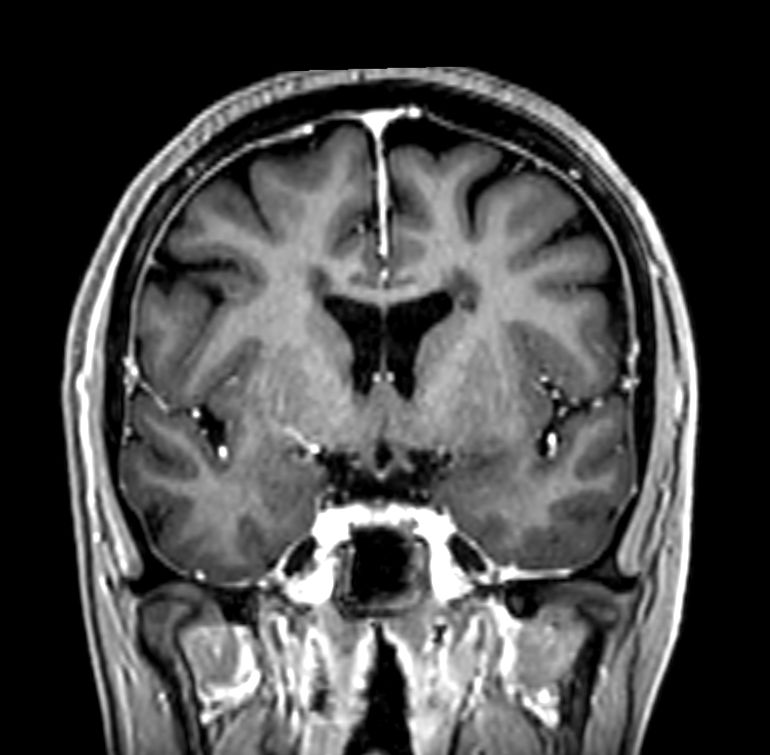

Multiple Sclerosis versus TIA

Standardized Multiple Slerosis MRI protocols typically require long scan times. Addition of Compressed SENSE enables faster exams, without compromise in image quality1. SWIp sequence has a high sensitivity to enhance contrast for deoxygenated (venous) blood or calcium deposits. This may help, when used in combination with other clinical information, in the diagnosis of various neurological pathologies. 3D (BrainVIEW) lets you acquire high resolution data in multiple directions in one scan. Isotropic voxel size enables reformats in any plane without loss of resolution.

3D T1w FFE Compressed SENSE